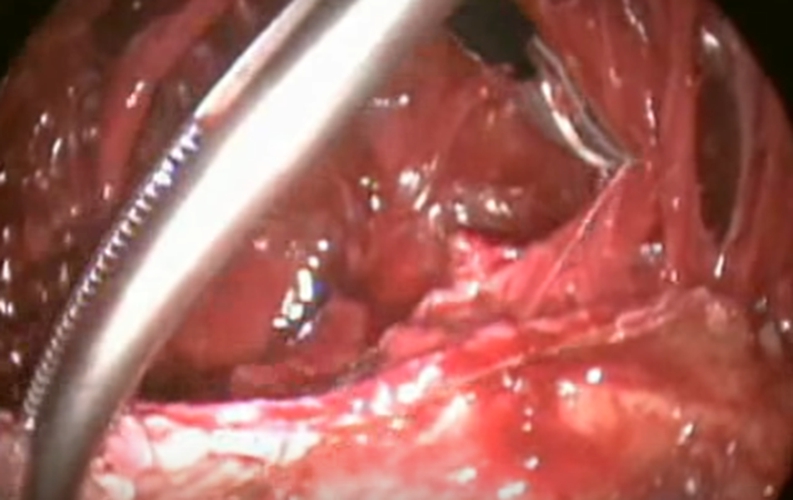

結核性胸膜炎胸腔鏡

結核性胸膜炎胸腔鏡的